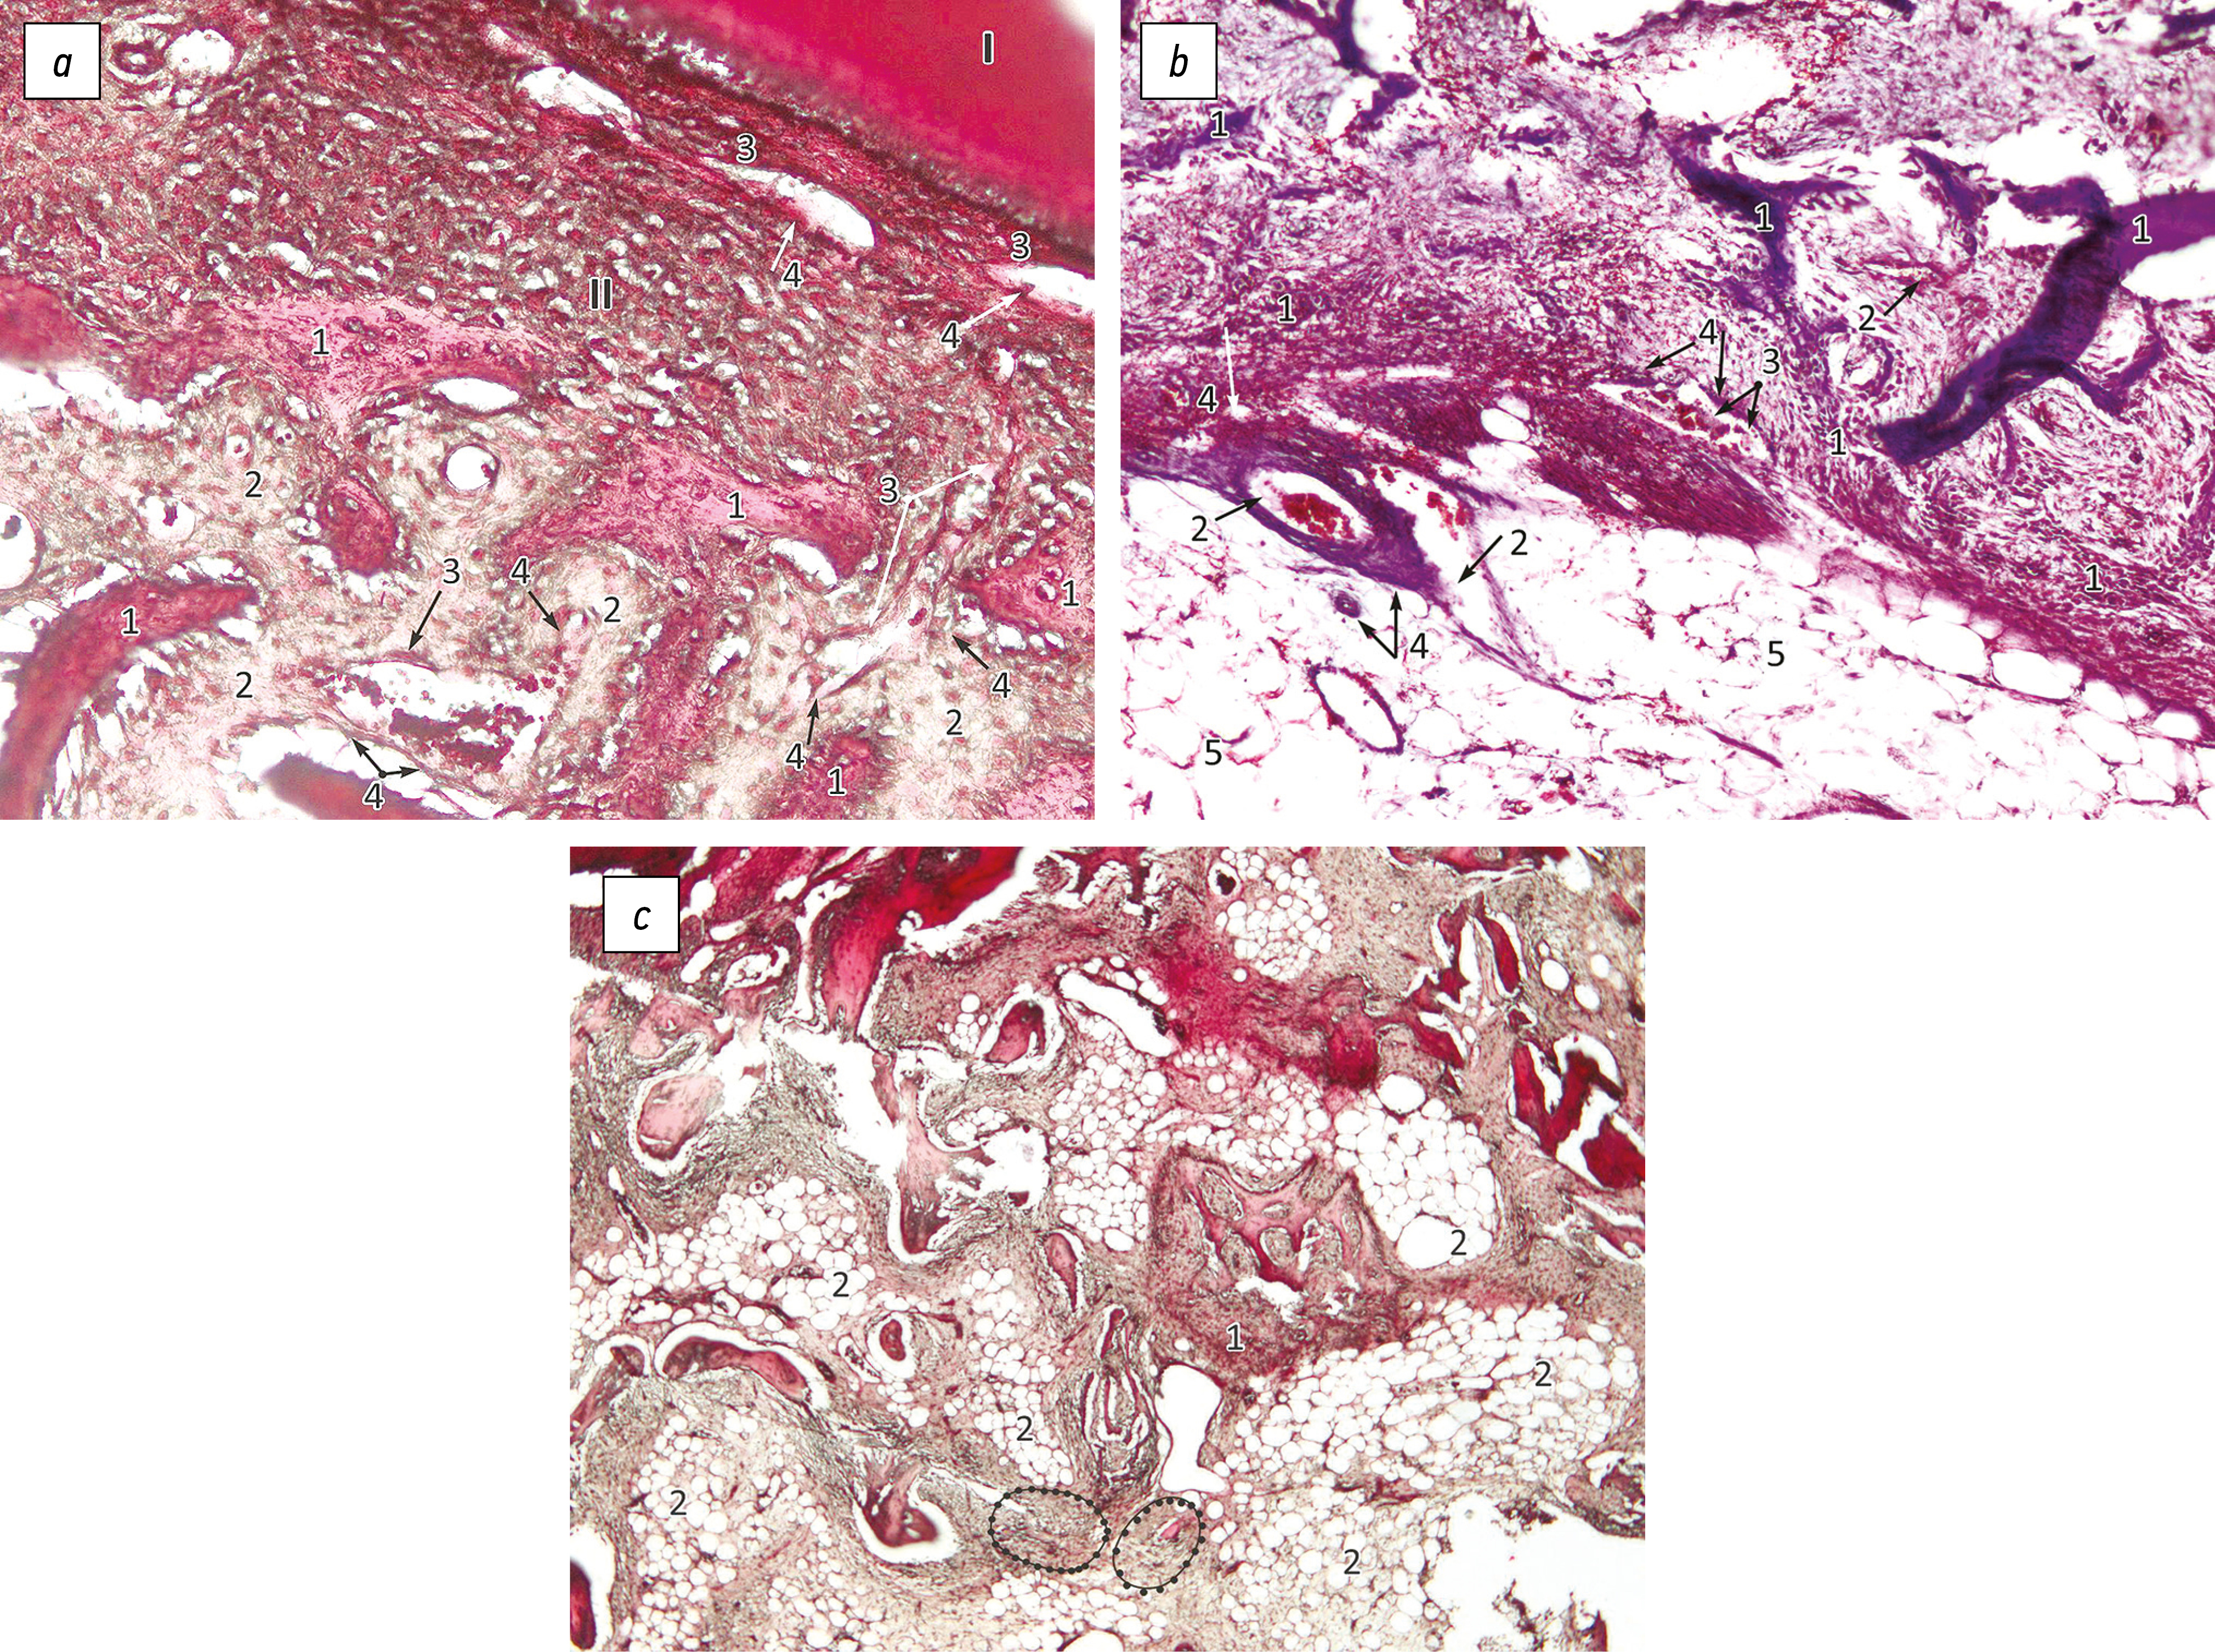

Рис. 1. Морфологическая картина формирования тканей альвеолярного дефекта с ацеллюлярным дермальным матриксом (АцДМ) и барьерной мембраной:

a — в поверхностном участке, ×100, окраска гематоксилином и эозином; I — эпителий, II — нерезорбируемая барьерная мембрана, III — ацеллюлярный дермальный матрикс; 1 — синусоидальные капилляры, 2 — трансваскулярная миграция клеток, 3 — эффекты слияния гранулоцитов в длинные клеточные агрегаты, 4 — формирование ретикулярной соединительной ткани;

b — в глубоком участке, ×200, окраска гематоксилином и эозином; 1 — синусоидальные капилляры, 2 — формирование ретикулярной стромы в межбалочных пространствах, 3 — клетки-выстилки, 4 — дифференцировка клеток в остеобласты и эффекты клеточного слияния, 5 — первичные костные балки;

c — окраска по Массону, ×200; 1 — синусоидальные капилляры, 2 — клеточная выстилка первичных костных балок, 3 — участок дифференцировки гранулоцитов в выстилающие и другие активные клетки, 4 — дифференцировка клеток в остеобласты и эффекты клеточного слияния.

В образцах группы 1 покровную ткань дефекта отличают сниженное количество ростковых слоёв эпителия, неравномерная кератинизация пласта, отсутствие клеточной анизоморфии без признаков формирования сосочкового слоя эпителия, наличие прерывистого базального слоя (рис. 1, a)2. Дермографт к окончанию эксперимента сохранил свою исходную толщину при качественном перестроении поверхности как основы для формирования новых структур. Под барьерной мембраной определяются небольшие синусоидальные капилляры (рис. 1, a, 1) с созревающими гемопоэтическими клетками в виде островков. Визуализируется выход из них оксифильно окрашенных неприкреплённых клеток в окружающую ткань (рис. 1, a, 2): посредством цитоплазматических отростков-мостиков клетки мигрируют трансваскулярно, чаще группами, через имеющиеся бреши (поры) в стенках синусоидальных капилляров. Быстрое увеличение количества и изменения морфологии клеточных форм в тканях обнаруживается в виде множества мелких базофильно окрашенных сегментоядерных, реже — палочкоядерных, нейтрофильных лейкоцитов, как и более крупных переходных промежуточных клеток с разной степенью интенсивности окраски. Хорошо визуализируются процессы слияния части гранулоцитарных элементов с возникновением клеток, содержащих несколько тёмных ядер и вытянутую уплощённую цитоплазму (рис. 1, a, 3). В виде длинных лиловых тяжей или более тонких цитоплазматических отростков они формируют стенки новых синусоидальных капилляров, как и трофических сосудов, а также выстилают поры и неровности АцДМ, располагаясь поверх ранее сформированных коллагеновых волокон матрикса дермографта. Такие клеточные агрегаты взаимодействуют с крупными фибробластоподобными клетками в разветвлённой структуре матрикса (рис. 1, a, 4), увеличивая толщину формируемых тканей за счёт продукции органической субстанции как связующей основы. В зонах образования ретикулярной ткани костного мозга клетки-выстилки участвуют в формировании более контрастно окрашенных клеток треугольной формы, что хорошо определяется в нижерасположенных межтрабекулярных пространствах, а также в поверхностных подмембранных участках в виде очаговых образований.

Крупный фрагмент синусоидального дерева и несколько небольших гемокапилляров образованы в интерпозиции АцДМ и зоне первичных костных балок (рис. 1, b, 1): после миграции миелоидных клеток-предшественников из гемокапилляров происходит запуск процессов клеточной пролиферации и дифференцировки (с изменением морфологии) в вышеописанной последовательности событий, отличаясь лишь отсутствием в этой зоне дермоматрикса. Сформированная ретикулярная соединительная ткань образует строму кроветворного костного мозга в зоне костного дефекта (рис. 1, b, 2, 3, 5). Ретикулярные клетки взаимодействуют между собой и с другими клетками микроокружения — переходными промежуточными формами — посредством широких цитоплазматических филоподий, образующих сетеподобную структуру. В ней прослеживаются прямое взаимодействие с клетками-выстилками, а также активность процессов клеточных слияний, что предваряет дифференцирование в остеобласты — крупные клетки полигональной формы, с резко базофильными ядрами с несколькими ядрышками (рис. 1, b, 4).

Последующие клеточные активации в костномозговой межбалочной структуре при увеличении молодой кости в толщину происходят за счёт аппозиционного роста. Базофильно окрашенные клетки эндостального слоя, среди которых хорошо видны остеобласты-строители и гранулоцитарные клеточные формы, соединённые длинными отростками, перемещаются внутрь структуры ретикулофиброзных костных балок. Часть остеобластических клеток приобретает функции остеоцитов (cм. рис. 1, b; рис. 1, с). Эти эффекты остаются заметными и позже — в зрелой пластинчатой кости альвеолярного челюстного гребня — как неминерализованные или слабо минерализованные межфазные промежутки, вдоль которых откладываются кристаллы апатита, как по трафарету [23].